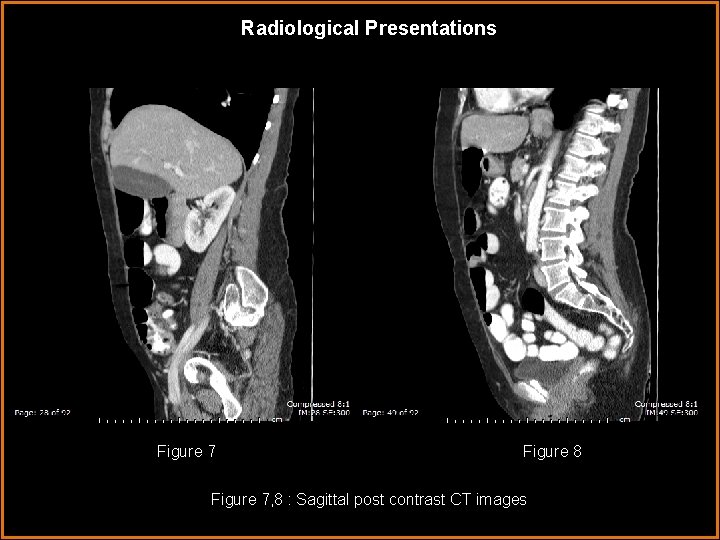

Radiological Presentations Figure 7 Figure 8 Figure 7, 8 : Sagittal post contrast CT images

Findings and Differentials Findings: CT: There is dilatation of the 1 st-3 rd portions of the duodenum up to 5 cm with a transition point where the duodenum crosses between the aorta and superior mesenteric artery. The aortomesenteric distance as measured on the axial images where the duodenum crosses the aorta is approximately 7. 3 mm (figure 15) and the aortomesenteric angle as measured on the sagittal images measures approximated 15 o (figure 16). A hiatus hernia was present on images not presented.

Discussion As previously mentioned, the aortomesenteric angle and distance are decreased in patients with SMA syndrome. Patients with SMA syndrome have aortomesenteric distances of 2 -8 mm whereas the normal range is 10 -28 mm. Similarly, patients with SMA syndrome have decreased aortomesenteric angles of 6 -22 o whereas the normal range is 25 -60 o. 3 -7 These measurements have traditionally been obtained with angiography, but today they are more commonly obtained with CT. CT is noninvasive and is more effective at evaluating for other causes of duodenal dilation than conventional angiography. Also, if the SMA is anterolateral rather than directly anterior to the aorta, lateral projection angiography may underestimate the true aortomesenteric distance. 6 -7 In the presented case, many of the radiographic and clinical features of SMA syndrome are present. The patient presented with symptoms of high intestinal obstruction including bilious vomiting. On CT the duodenum was dilated with a transition point at the 3 rd portion and both the aortomesenteric distance and aortomesenteric angle were decreased measuring 7. 3 mm and 15 o respectively. On upper GI there was also a dilated duodenum with the suggestion of an abrupt vertical cutoff of contrast at the 3 rd portion just to the right of the spine.